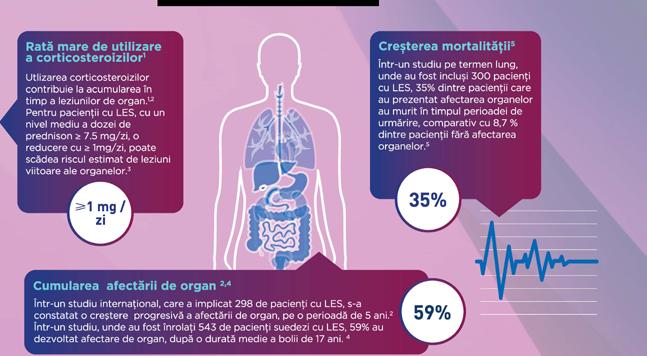

Afectarea ireversibila a organelor si mortalitatea crescuta continua sa fie ' o preocupare pentru pacientii cu LES. 2•4•

Referinte: 1. Peschken CA, et al. Persistent disease activity remains a burden for patients with systemic lupus erythematosus. J Rheumatol 2019;46(2):166-175; 2. Urowitz MB, et al. Evolution of disease burden over five years in a multicenter inception systemic lupus erythematosus cohort Arthritis Care Res (Hoboken) 2012;64(1):132-137; 3 Al Sawah S, et al. Effect of corticosteroid use by dose on the risk of developing organ damage over time in systemic lupus erythematosus-the Hopkins Lupus Cohort. Lupus Sci Med 2015;2(1):e000066;

4. Frodlund M, et al The majority of Swedish systemic lupus erythematosus patients are still affected by irreversible organ impairment: factors related to damage accrual in two regional cohort. Lupus 2019;28(10):1261-1272; 5. Segura BT, et al Damage accrual and mortality over long-term follow-up in 300 patients with systemic lupus erythematosus in a multi-ethnic British cohort. Rheumatology (Oxford) 2020;59(3):524-533.